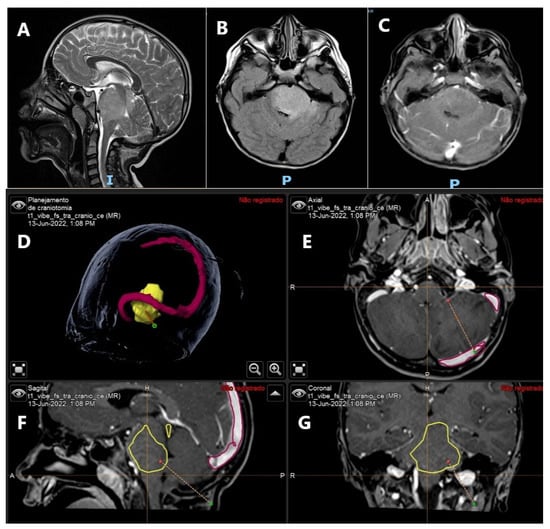

- Markopoulos, G.S.; Goussia, A.; Bali, C.D.; Messinis, T.; Alexiou, G.; Vartholomatos, G. Resection Margins Assessment by Intraoperative Flow Cytometry in Pancreatic Cancer. Ann. Surg. Oncol. 2022, 29, 4643–4645. [Google Scholar] [CrossRef]